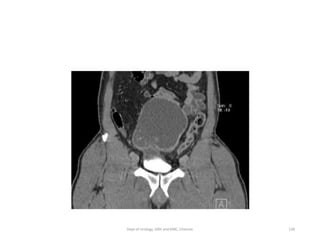

• Midline,

• soft-tissuemass with calcification ( Stippled )

consideredto be urachal adenocarcinoma until

proved otherwise.